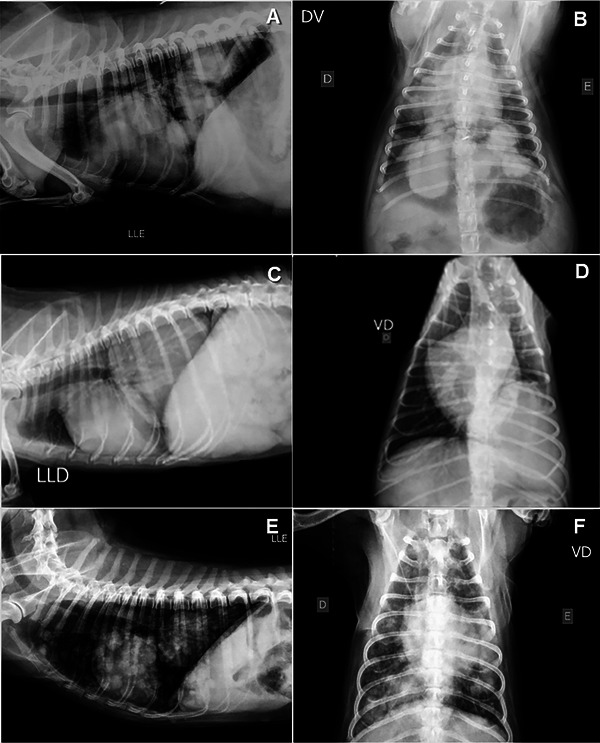

本研究旨在评估声辐射力脉冲(ARFI)弹性成像作为狗肺部病变诊断工具的应用。该研究包括在2020年至2022年期间被兽医教学医院放射科检查肺部病变的狗。肺病变的特征评估使用x线摄影作为定位的筛选工具,b超用于组织表征,随后进行定性(弹性图等级1-3)和定量(剪切波速- swv)弹性图评估。根据临床、超声、影像学、组织病理学和/或细胞学检查结果,将病变分为以下几类:实变、肺不张或肿瘤(结节和肿块)。26只狗符合资格标准,被纳入研究。在某些情况下,同一只狗有不止一种类型的病变,导致35个肺病变的评估:13个肿块,8个结节,8个实变,4个肺不张区。定量弹性成像评估显示,与实变(2.94±0.64 m/s)、结节(2.85±1.40 m/s)和肿块(3.13±1.45 m/s)相比,肺不张病变的刚度(1.48±0.35 m/s)较低,但由于良性病变数量有限,没有明确的诊断临界值。结果表明,ARFI弹性成像可以作为一种有价值的补充工具,与临床数据和传统成像技术一起评估狗的肺部病变。未来的研究需要更大样本量的良性肺实质病变,以进一步探索弹性成像预测恶性肿瘤的潜力。

This study aimed to evaluate the use of acoustic radiation force impulse (ARFI) elastography as a diagnostic tool for lung lesions in dogs. Dogs referred to the Radiology Department of the Veterinary Teaching Hospital between 2020 and 2022 for the detection of lung lesions were included in the study. The characteristics of the lung lesions were assessed using radiography as a screening tool for localization, B-mode ultrasound for tissue characterization, and subsequently, both qualitative (elastogram grades 1-3) and quantitative (shear wave velocity-SWV) elastographic evaluations. The lesions were classified based on clinical, ultrasound, radiographic, histopathological, and/or cytological findings into the following categories: consolidations, atelectasis, or neoplasms (nodules and masses). Twenty-six dogs met the eligibility criteria and were included in the study. In some cases, the same dog had more than one type of lesion, resulting in the evaluation of 35 lung lesions: 13 masses, 8 nodules, 8 consolidations, and 4 areas of atelectasis. The quantitative elastographic evaluation revealed lower stiffness in atelectatic lesions (1.48 ± 0.35 m/s) compared with consolidations (2.94 ± 0.64 m/s), nodules (2.85 ± 1.40 m/s), and masses (3.13 ± 1.45 m/s), although no definitive diagnostic cut-off value was established, due to the limited number of benign lesions. The results suggest that ARFI elastography can be a valuable complementary tool alongside clinical data and conventional imaging techniques in assessing lung lesions in dogs. Future studies with a larger sample size of benign parenchymal lung lesions are needed to further explore the potential of elastography for predicting malignancy.